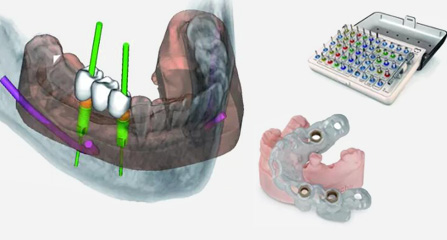

福能海峡口腔着眼于全链条的数字化诊疗解决方案,与德国ICX、瑞典Nobel、韩国奥齿泰等国际知名齿科品牌合作,建立“福州数字化口腔联盟”,应用全数字化口腔模式,从CBCT数据提取、AI口扫取模、AI智能口腔体检、数字化分析模拟与方案设计、3D打印、CAD/CAM椅旁加工以及手术模拟导航等,全流程打通数字化口腔精确诊疗的各个环节,实现福能海峡数字化口腔诊疗体系新升级。

云端3D打印 导板辅助

动态导航监测 精确控制植入路径

DSD设计 专属迷人微笑

• 仿生修复美学设计 外冠以假乱真

一体化CAD/CAM义齿加工